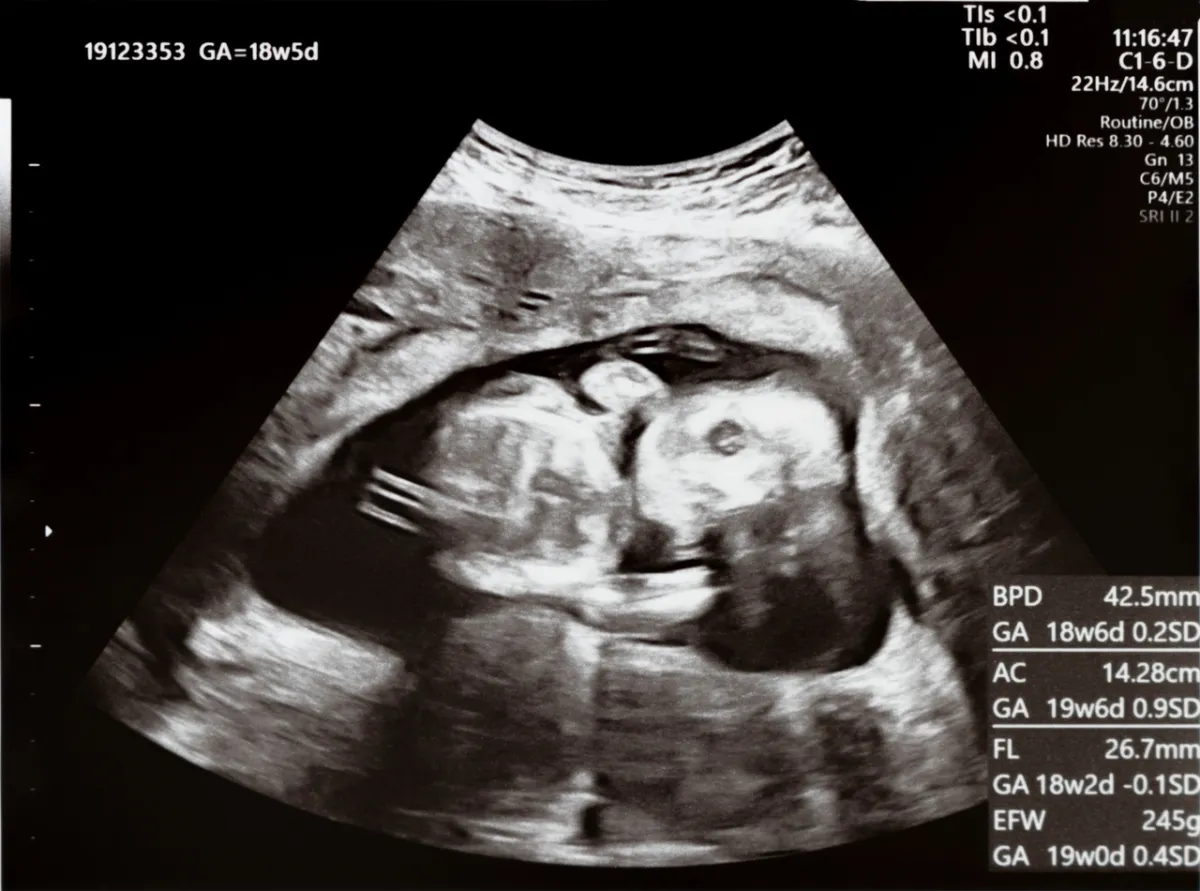

كيف ينمو طفلي خلال هذا الشهر؟

الآن، سوف يستقر الجنين داخل رحمك، وستبدأ أعضاء الطفل في النمو. فيما يلي لمحة بسيطة على نمو طفلك:

الرأس: سيكون رأس طفلك أكبر قليلاً من الجسم بسبب نمو دماغه.

الجفون: سوف تغطي الجفون عيون طفلك بالكامل لحمايتها.

الفم: تبدأ حنجرة طفلك ولسانه في النمو. كما يتم تشكيل فكيه وشفتيه العلويتين.

الإبهام: سيبدأ طفلك في مص إبهامه في هذه المرحلة ويبدأ في الإصابة بالحازوقة.

القلب: ينمو قلب طفلك الصغير ولديه الآن نبضات قلب يمكن سماعها من خلال أجهزة المراقبة الإلكترونية.

الجهاز العضلي الهيكلي: يتشكل الجهاز العضلي لطفلك مع بدء تصلب بعض العظام. ومع ذلك، لا يزال العمود الفقري طريًا.

الأطراف: تنمو أصابع يدي وقدمي طفلك الصغير كما تنمو أظافر هذه الأصابع والأصابع الصغيرة خلال هذا الشهر أيضاً.

الحركات: تذكّري أن الكثير يحدث في داخلك، لكنك لن تشعري بذلك بعد. سيبدأ طفلك النامي في الركل، التمدد، الالتواء والدوران. نظرًا لأن رحمك لا يزال فوق الحوض، فقد لا تشعرين بهذه الحركات بعد.